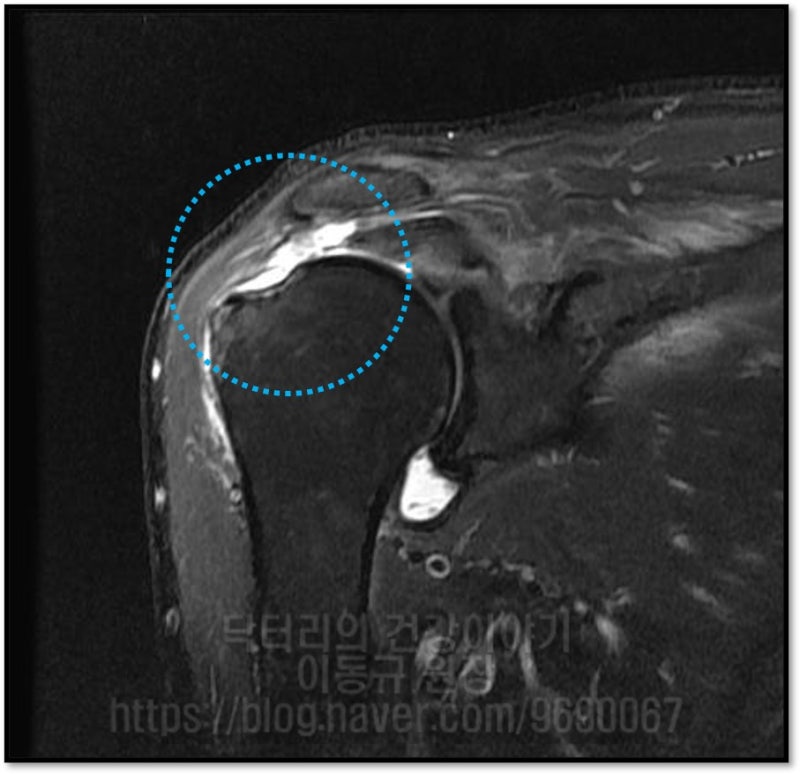

등등 말씀을 하십니다. 왜 정확히 진단을 하지 않고 왜 제대로 된 치료를 하지 않는 걸까요? 오늘 말씀드릴 케이스는 83세 환자분 입니다. 환자분은 어깨가 아파서 동네 병원에 갔는데 염증 있다고 아프면 주사맞고 좀 괜찮다가 또 아프고....그럼 또 주사 맞고... 이런 것을 3년 동안 해 왔다고 하였습니다. 그런데 이제는 주사 맞아도 효과도 없고 점점 더 아파지면서 가동범위 제한까지 와서 일상생활이 힘들고 밤에 아파서 잠을 못잔다고 하시면서 제발 고쳐달라고 하시면서 저한테 오셨습니다. 검사를 진행하였습니다.

환자분이 나이가 83세 이시지만 치료의 의지가 있고 건강상태도 좋았고 수술적 치료를 하였습니다.

나이는 숫자에 불과합니다. 이 환자분의 경우도 회전근개가 건강하여 봉합을 하여도 튼튼하게 봉합되었습니다.